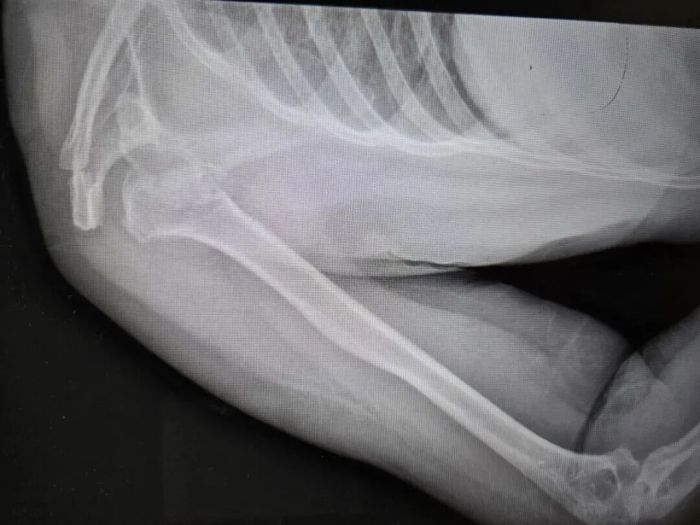

近日,河南50岁的张大姐在睡梦中粉碎性骨折,肩膀骨头碎成七八块,丈夫称妻子全程都在床上躺着。

河南省人民医院创伤骨科主任刘涛称:“第一反应不敢相信,高空坠落、车祸撞击才会有这么大的力。”像张大姐这样癫痫导致粉碎性骨折临床及文献中都极罕见。

诊疗小组制定方案,将劈裂的肱骨骨头、后脱位等四大部分、七八块碎裂的骨头都按原貌实现完整复位,并将受损的肌腱完全修复,将塌陷的部分填充了支撑骨。目前,张大姐正在进一步接受癫痫相关管理与规范治疗。